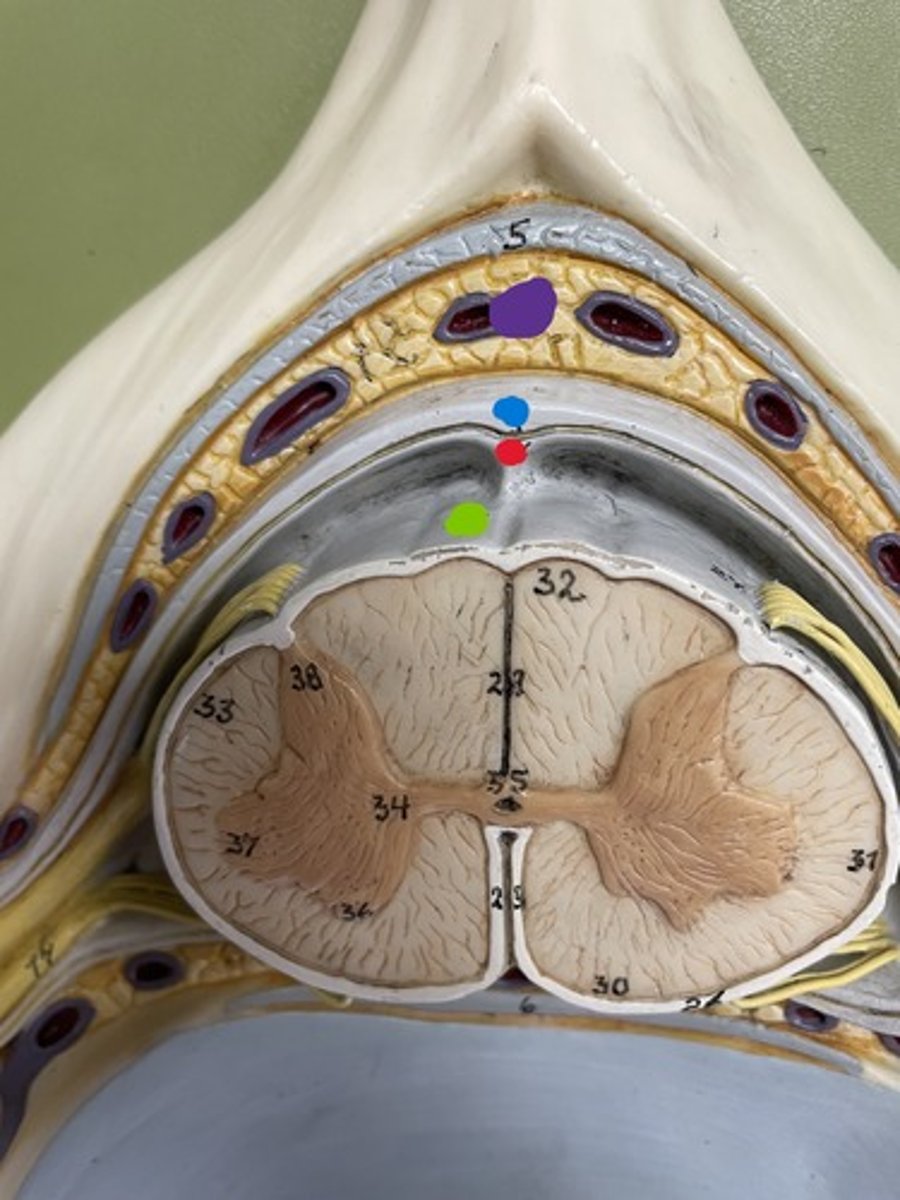

Dura mater

blue

Arachnoid mater

red

Pia mater

green

Epidural space

purple

Subdural space

between red and blue

Subarachnoid space

between red and green